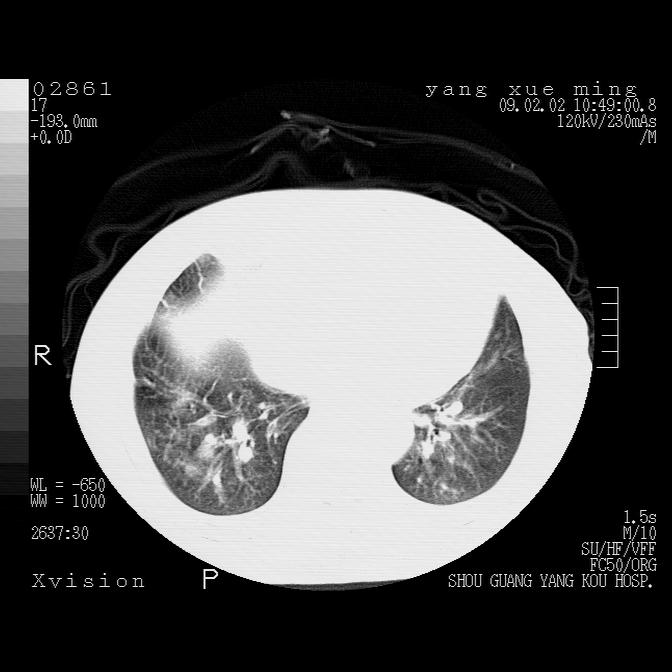

以下是引用zbp537在2009-2-3 19:08:00的发言:[br]我诊断为肺泡性肺水肿。[br]诊断依据:[br]1、心影普遍增大,肺血管增粗,并见絮状高密度影,肺门改变显著。[br]2、临床上表现胸闷咳嗽,无发烧,不是一个典型的肺部感染的病史。

以下是引用lkc8963在2009-2-3 20:11:00的发言:[br]1)右上肺陈旧病灶。2)右下肺团块及团片影,影像表现符合感染。3)左心增大,左冠脉钙化,符合冠心病。4)双侧肺门扩大,以左侧为著,肺动脉干略粗,左上肺局限性气肿,为谨慎起见,需除肿瘤,建议增强。

以下是引用lkc8963在2009-2-3 20:11:00的发言:[br]1)右上肺陈旧病灶.2)右下肺团块及团片影,影像表现符合感染.3)左心增大,左冠脉钙化,符合冠心病.4)双侧肺门扩大以左侧为著,肺动脉干略粗,左上肺局限性气肿,为谨慎起见,需除肿瘤,建议增强.